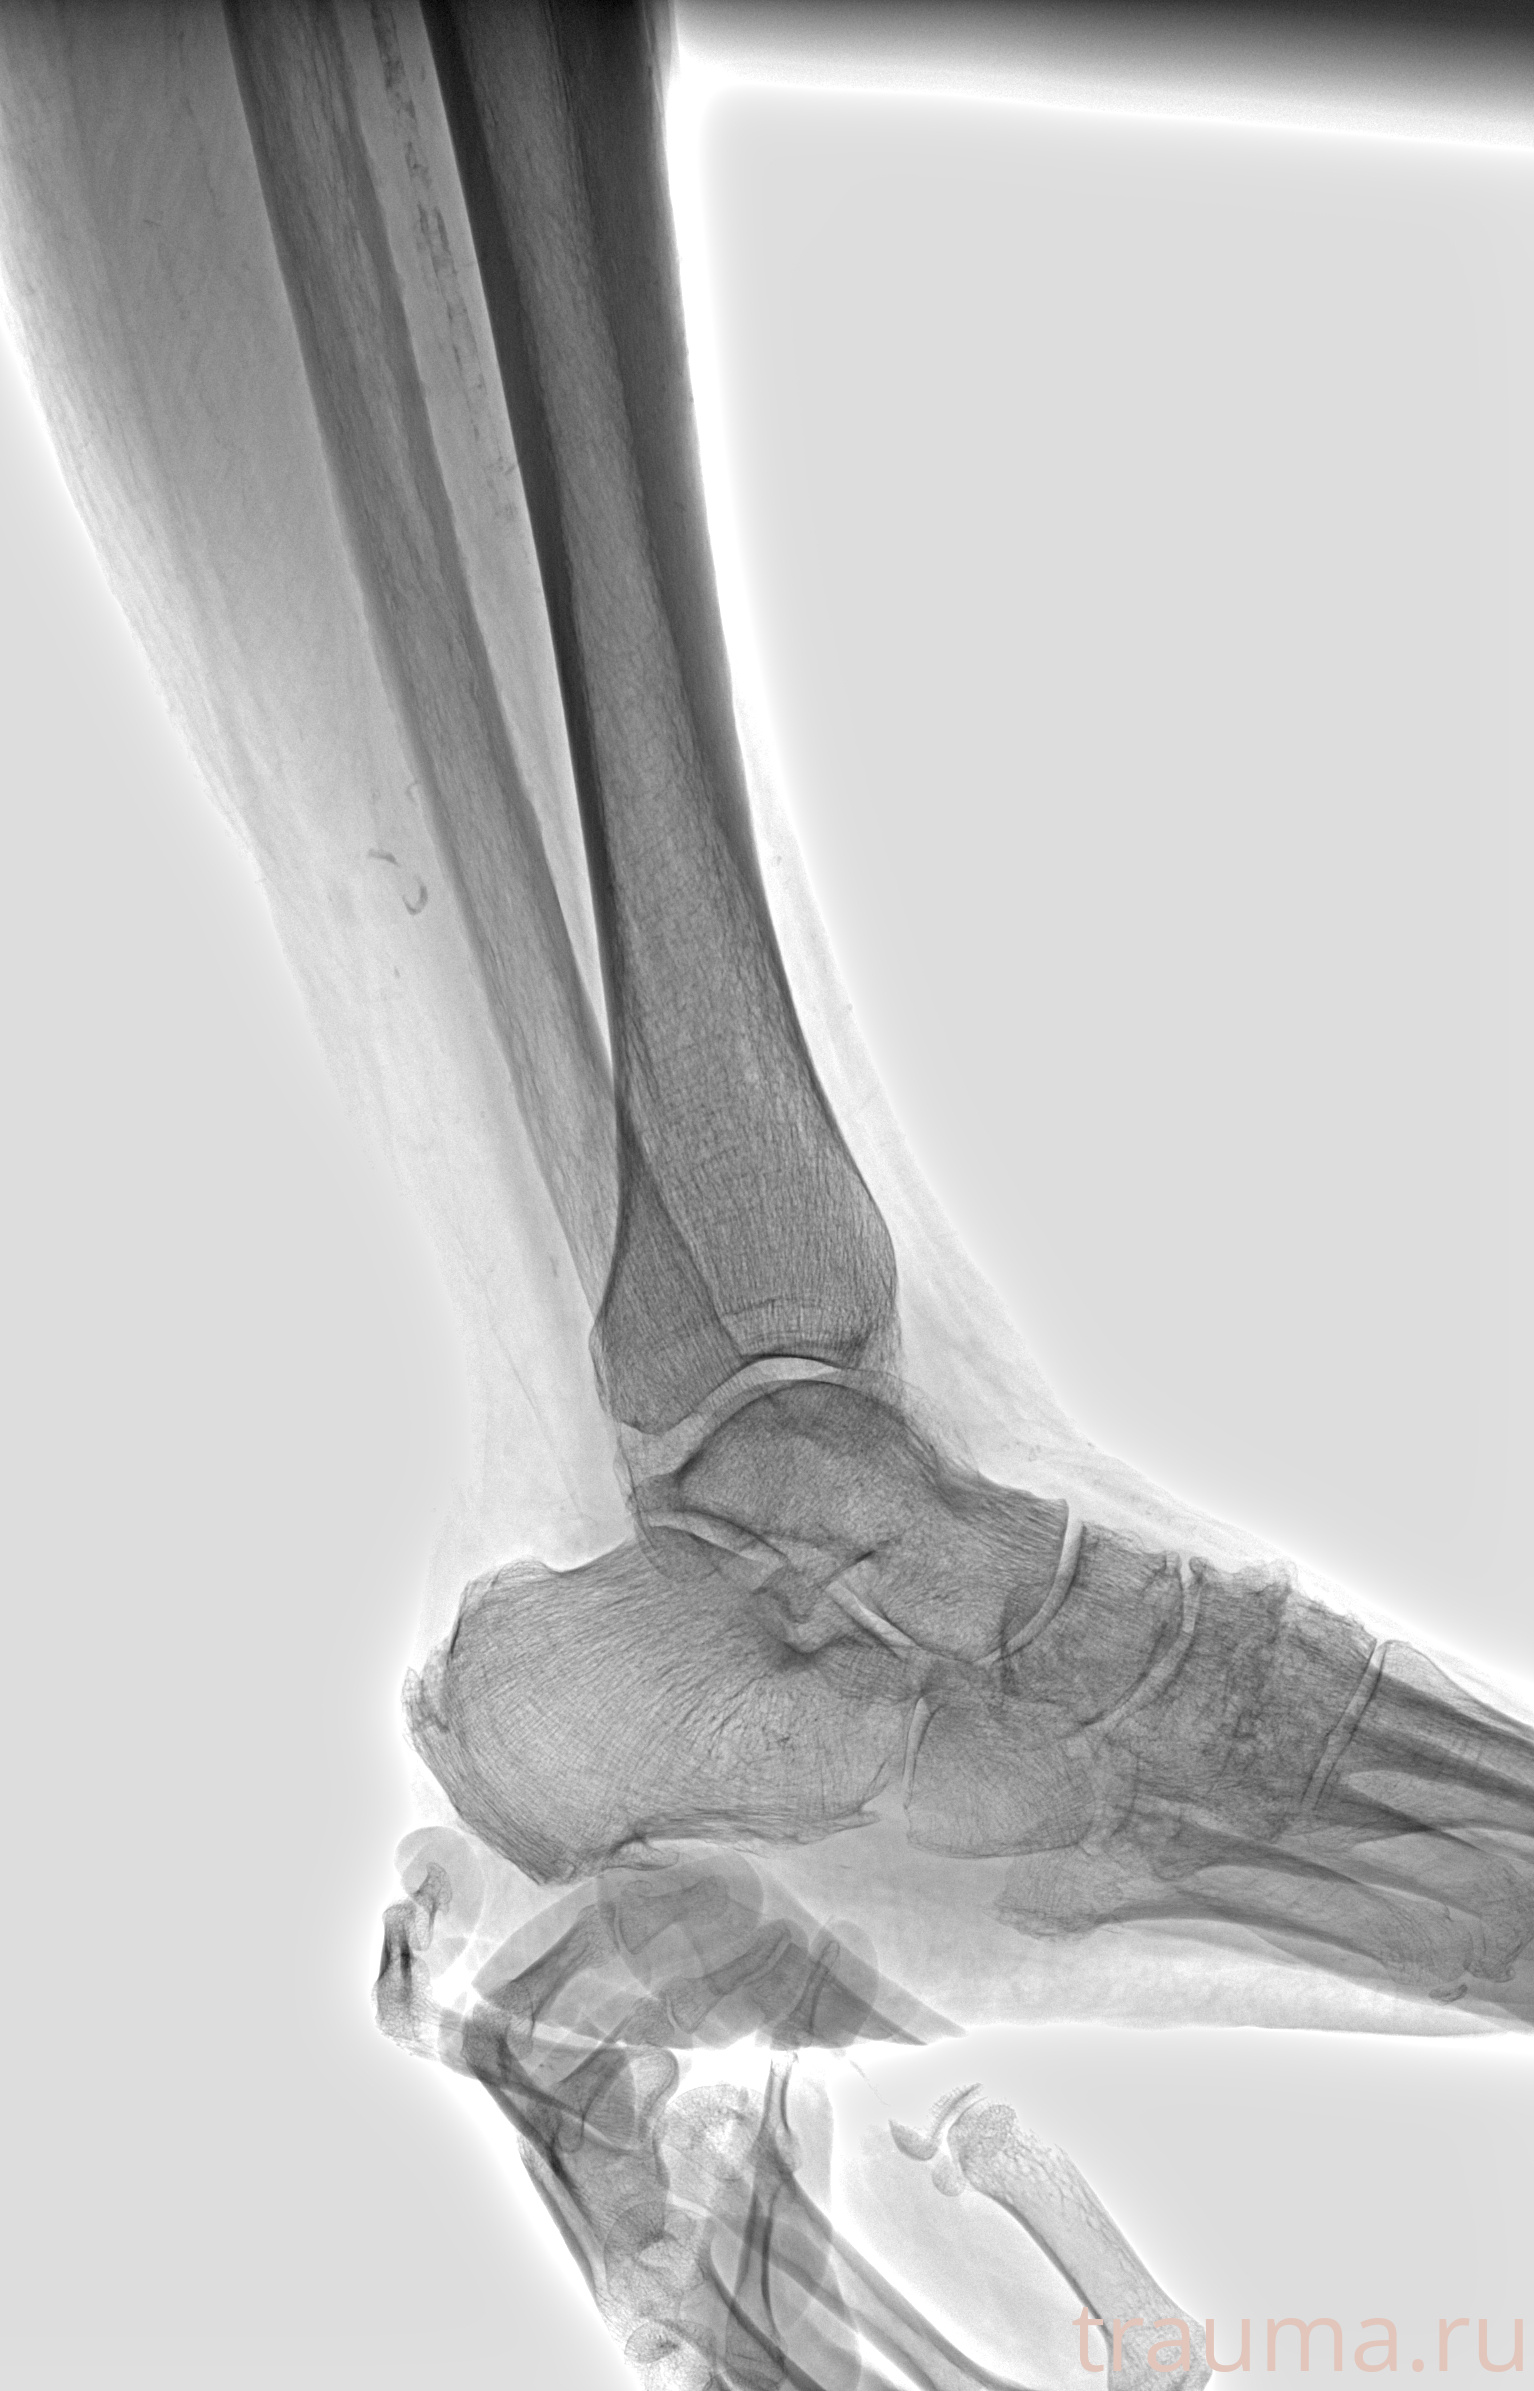

Рентгенограммы

Рентген на дому: по вашему адресу приезжает врач-рентгенолог, травматолог-ортопед с мобильным рентгеновским аппаратом, проводит диагностику травмы или заболевания, делает необходимые рентгенограммы, дает рекомендации по дальнейшему лечению. Получить качественные снимки в домашних условиях возможно благодаря уникальной методике, разработанной МосРентген Центром для института  Склифосовского

Яркость: 1   Контраст: 1   Инвертировать: 0 Увеличение: 1

Перетаскивайте мышь вверх/вниз для контраста, влево/право для яркости. Прокрутка колесом изменяет масштаб. Нажмите Сбросить для возврата к исходному изображению. При увеличении держите мышь в той области, которую хотите рассмотреть.